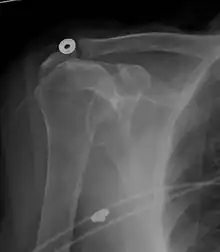

Xray

Projectional radiograph of normal glenohumeral position.[51]

High-riding humeral head in a rotator cuff tear.

X-ray projectional radiography cannot directly reveal tears of the rotator cuff, a 'soft tissue', and consequently, normal X-rays cannot exclude a damaged cuff. However, indirect evidence of pathology may be seen in instances where one or more of the tendons has undergone degenerative calcification (calcific tendinitis). The humeral head may migrate upward (high-riding humeral head) secondary to tears of the infraspinatus, or combined tears of the supraspinatus and infraspinatus.[51] The migration can be measured by the distance between:

• A line crossing the center of a line between the superior and inferior rims of the glenoid articular surface (blue in image).

• The center of a "best-fit" circle positioned over the humeral articular surface (green in image)

Normally, the former is positioned inferiorly to the latter, and a reversal therefore indicates a rotator cuff tear.[51] Prolonged contact between a high-riding humeral head and the acromion above it may lead to X-ray findings of wear on the humeral head and acromion; secondary degenerative arthritis of the glenohumeral joint (the ball and socket joint of the shoulder), called cuff arthropathy, may follow.[50] Incidental X-ray findings of bone spurs at the adjacent acromioclavicular joint may show a bone spur growing from the outer edge of the clavicle downward toward the rotator cuff. Spurs may also be seen on the underside of the acromion, once thought to cause direct fraying of the rotator cuff from contact friction, a concept currently regarded as controversial.